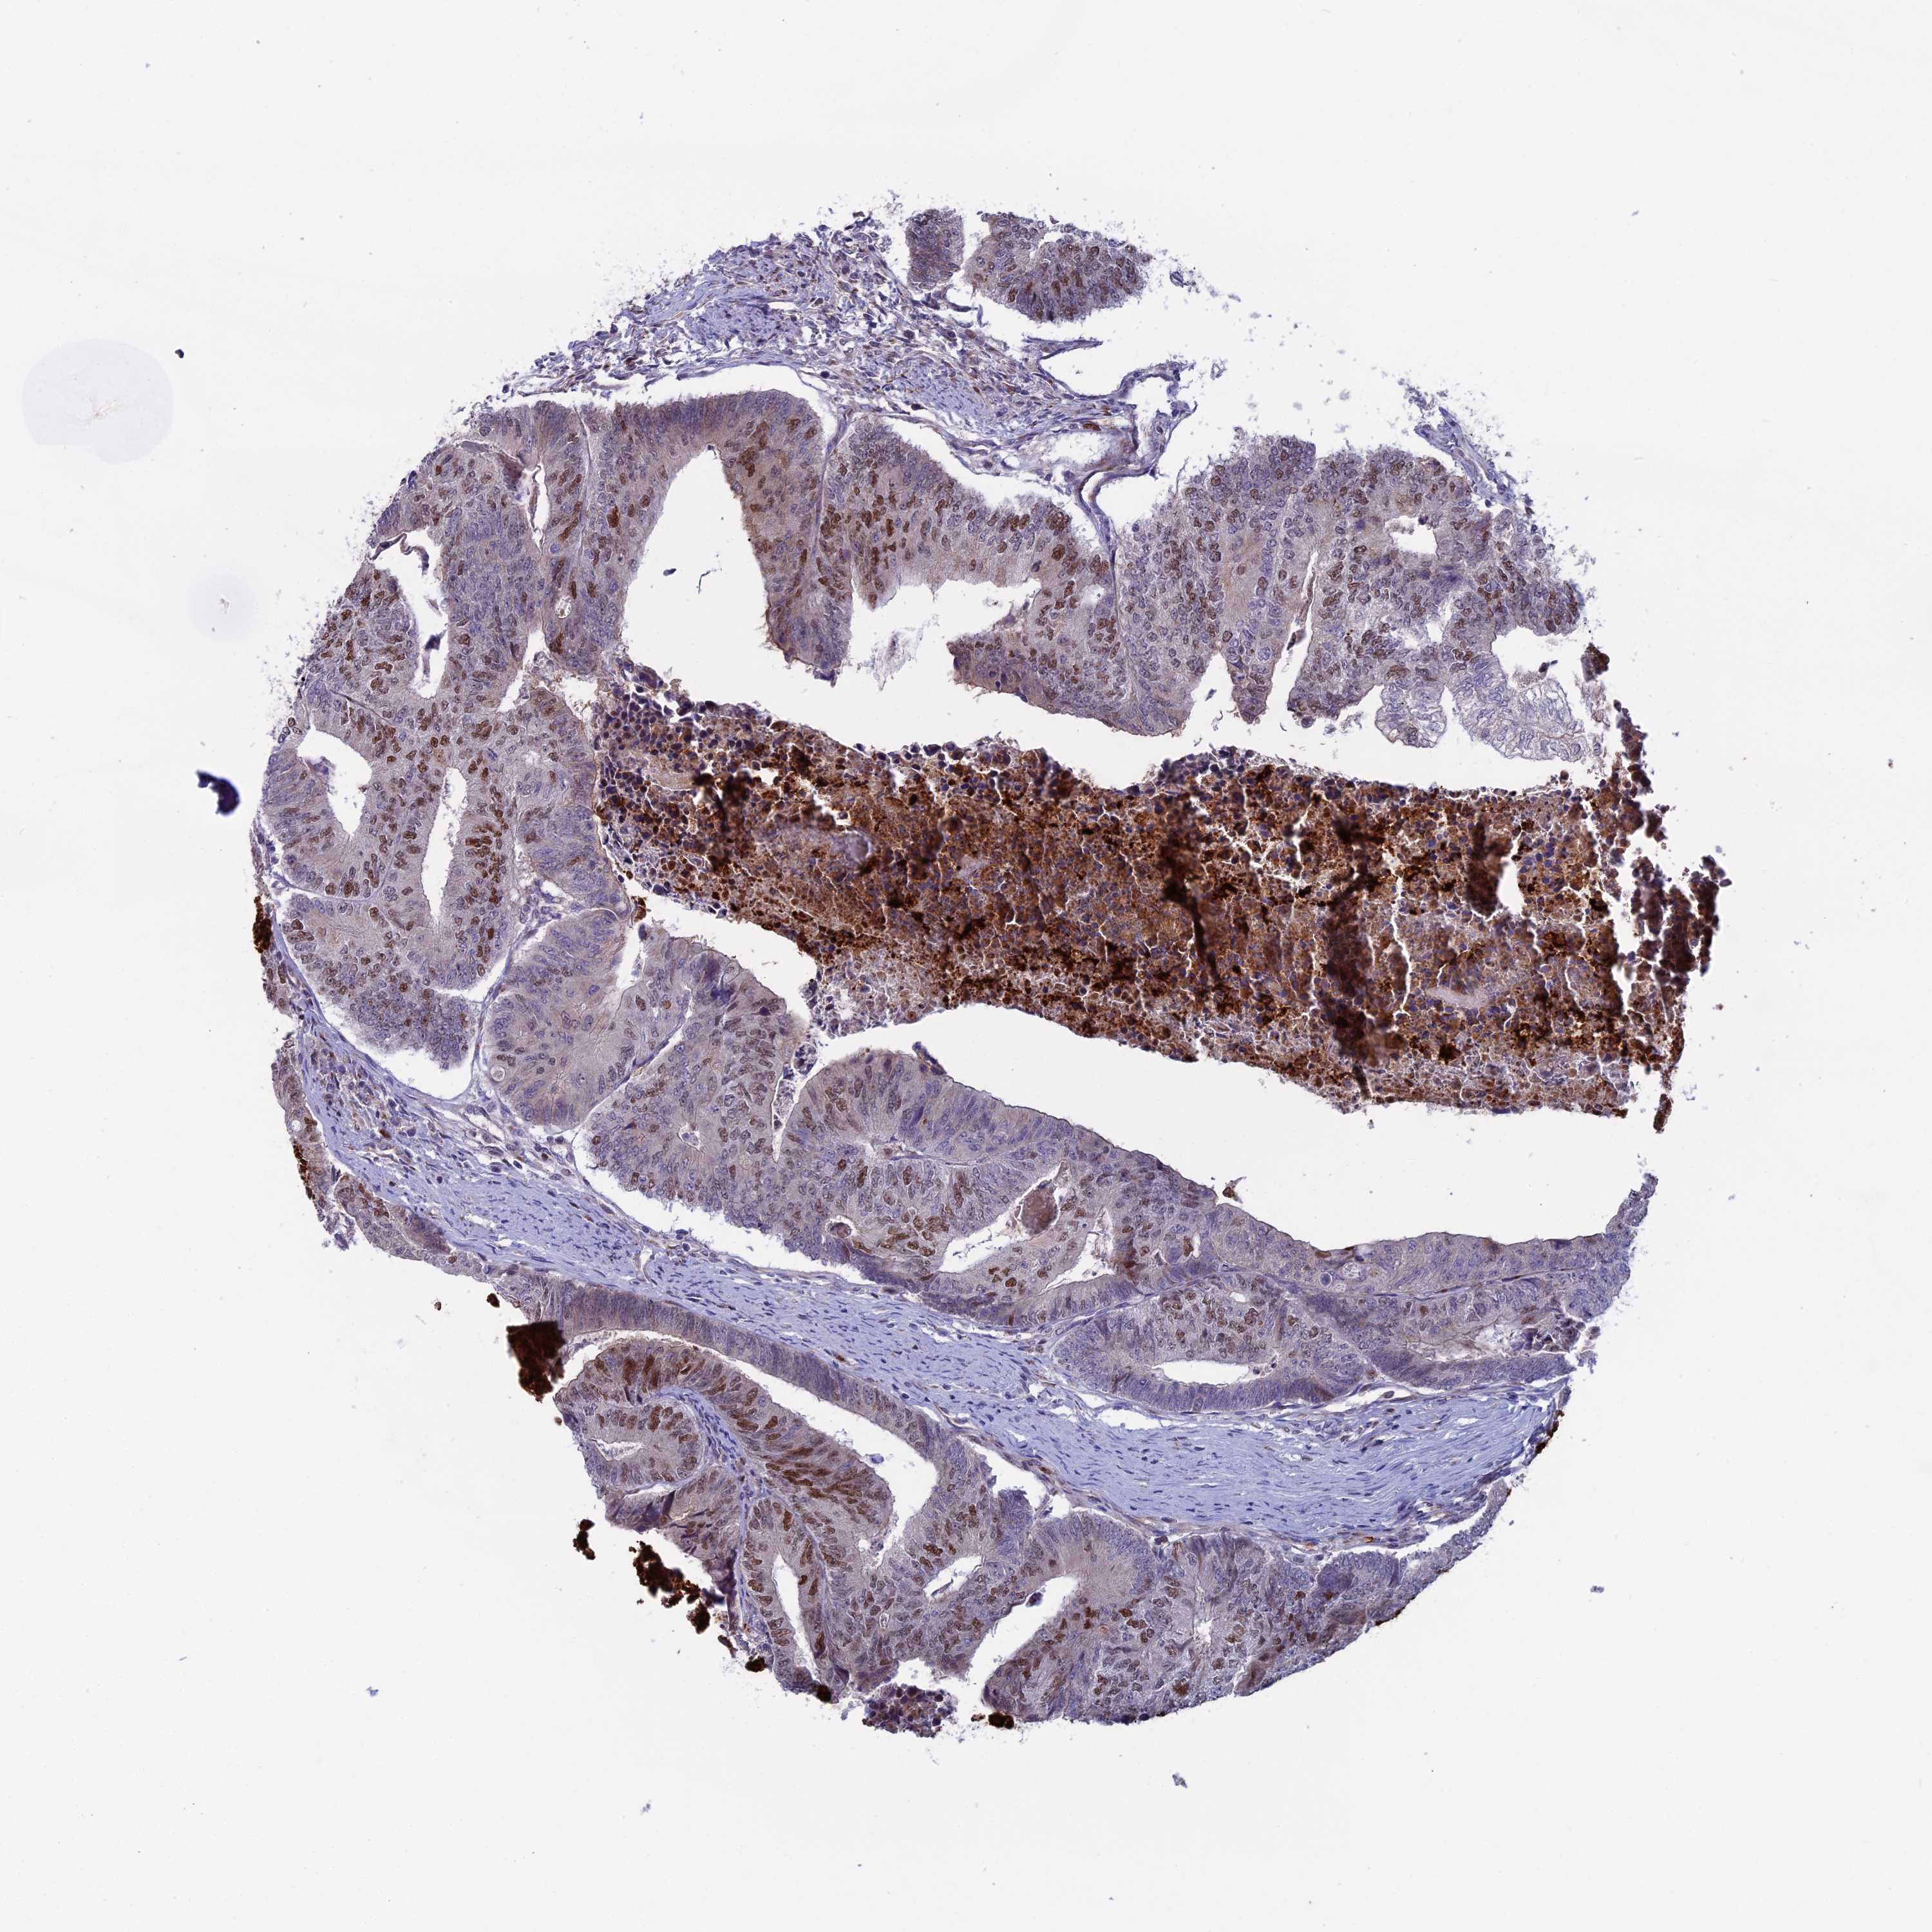

CANCER COLORECTAL CANCER Show tissue menu

ANTIBODIES

AND

VALIDATION

Colorectal cancer

Human cancer

Colon adenocarcinoma